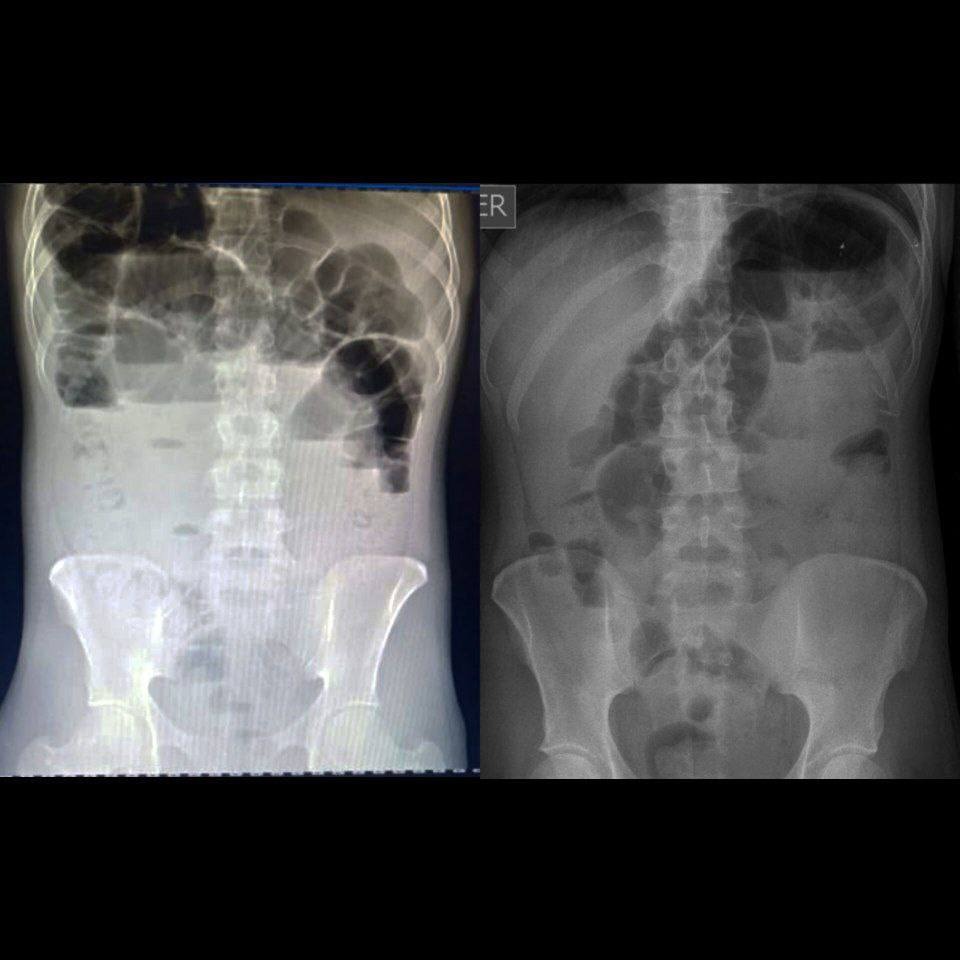

Recent medical evaluations have shown that he now has gallstones, which are hardened deposits that form in the gallbladder. While gallstones sometimes cause no symptoms, they can become extremely dangerous if they block bile ducts or cause inflammation. Among the possible complications are:

If left untreated, these complications can be life-threatening, especially in a system where urgent care is costly and must be paid for upfront. Medical professionals have advised that Aaron needs gallstone removal within the next two weeks to prevent potentially fatal outcomes such as infection, organ damage, or systemic inflammation, or even death.

This new development comes on top of an already difficult medical journey including complications from appendicitis, paralytic ileus, and medical malpractice. Your past support literally made a difference — and now we have to ask for help again to give Aaron the chance to get the life-saving surgery and follow-up care he urgently needs.

Gallbladder evaluation and diagnostic tests